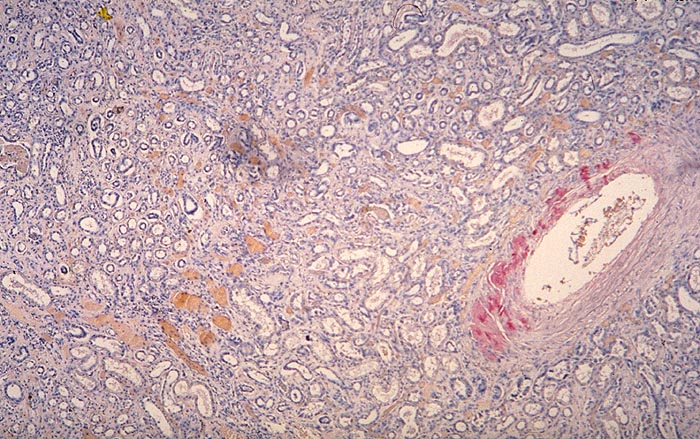

PathoPic ID 2029 - Amyloidose der Gefässe

Amyloidose der Gefässe

Systemerkrankung/Immunpathologie

Niere

Niere, Harnwege

Ausschliesslich Amyloidablagerungen in einer Arterienwand.

Glomeruli und Interstitium negativ. AL-Amyloid.

Histologie